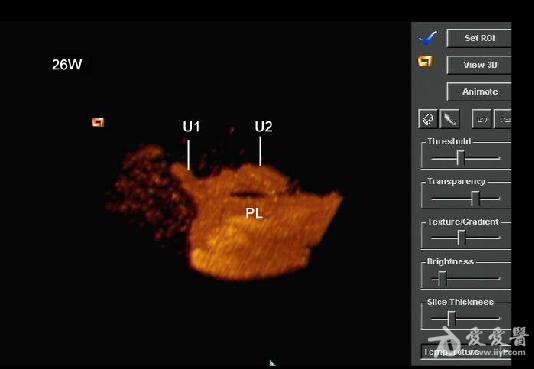

是双胎,其中畸形的那个明显没有上半身及头部,只有下半身和一点点短小的左上肢。

1、双胎中一胎形态、结构发育正常,另一胎出现严重畸形,以上部身体严重畸形为主,可有下部身体如双下肢等结构。

3、上部身体严重畸形,可表现为无头、无双上肢、胸腔发育极差。

4、部分无心畸胎上部身体结构难辨,仅表现为一不规则实质性团块组织回声,内部无内脏器官结构。

6、频谱及彩色多普勒血流显像可显示无心畸胎脐动脉及脐静脉内血流方向与正常胎儿相反,无心畸胎脐动脉血流从胎盘流向胎儿髂内动脉达胎儿全身,脐静脉血流从胎儿脐部流向胎盘,正好与正常胎儿脐动脉、脐静脉血流方向相反。